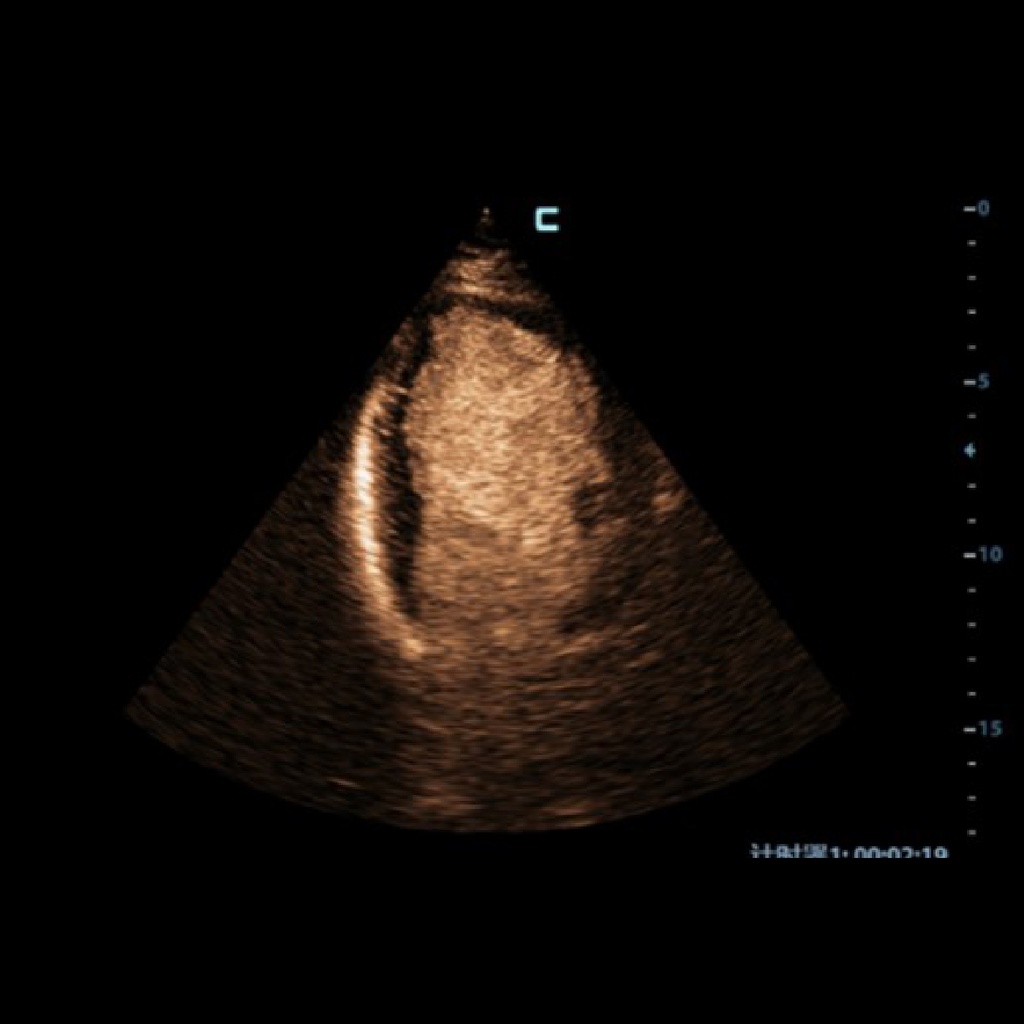

Открива стуктурни и функционални промени на лява камера с контраст. По-дълъг живот на контрастното вещество и по-висока чувствителност с UWN+